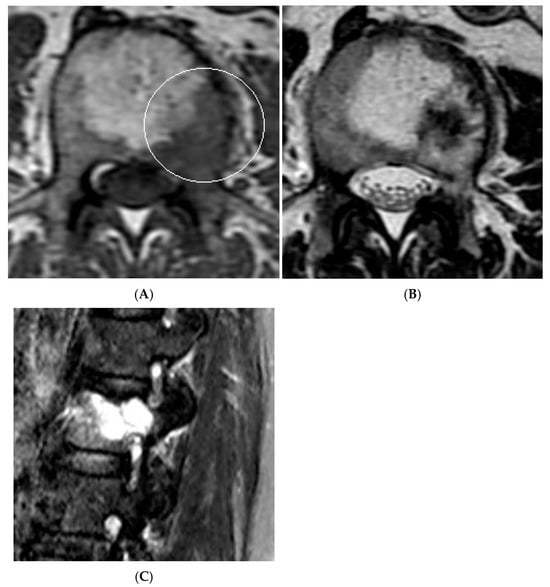

Figure 14.

Collision Lesions: Typical and atypical haemangioma of vertebral body. (A) Axial T1W MRI demonstrating a classic haemangioma with a T1 hyperintense lesion occupying the vertebral body, with a smaller atypical T1 hypointense lesion (circled) adjacent, in keeping with an atypical haemangioma. (B) Axial T2W MRI with the same lesions—the atypical lesion to the left side of the patient (vertebral body) has a higher vascular component and therefore is more hyperintense than the adjacent and larger typical haemangioma. The larger lesion still remains hyperintense on T2, in keeping with predominant internal fat content. (C) Sagittal T1W spine MRI. (D) Sagittal T2W spine MRI. (E) Sagittal STIR spine MRI demonstrating fat suppression within the typical haemangioma with hyperintense signal within the atypical haemangioma as a collision lesion example.